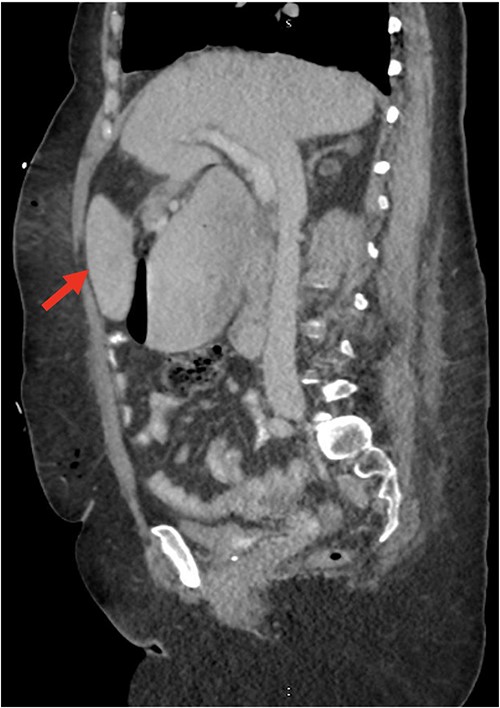

Despite the insertion of the NGT yielding 1500 cc output in 24 hours, the patient continued to experience severe abdominal pain. Urgent abdominal and pelvic computed tomography (CT) scans were taken, as seen in Figs 2–4. The CT scans showed gastric distension and the spleen positioned anteriorly in the right upper quadrant. Consequently, the decision was made to promptly bring the patient to the operating room for a diagnostic laparoscopy with plan to detorse the spleen.

CT of the abdomen and pelvis (axial slice) showing gastric distention and the spleen positioned anteriorly in the right upper quadrant.

Our patient’s pre-existing conditions presented challenges in distinguishing between expected postoperative discomfort and potential complications following her recent adrenalectomy. This uncertainty, combined with a normal WBC count, absence of fever, and regular bowel function, initially led the medical team to attribute her pain to the recent surgery two days prior, delaying her diagnosis and potentially exacerbating her condition. Subsequent imaging became imperative, revealing a persistent large gastric bubble despite NGT decompression, and malposition of the spleen (Fig. 3). This prompted immediate preoperative measures to facilitate a diagnostic laparoscopy.